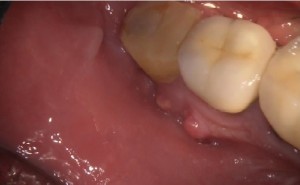

Endodontics is the medical term for root canal treatment and is only necessary when the nerve or pulp of the tooth becomes infected. The cause is neglecting a sensitive tooth that already has a hole. This neglect can make the tooth sore from time to time and the pain becomes severe which ends up in the face becoming swollen and a formation of an abscess. Root canal treatment also may be indicated after an injury or trauma. This situation is usually not known by the patient but the first signal a patient can face is most of the time severe toothache.